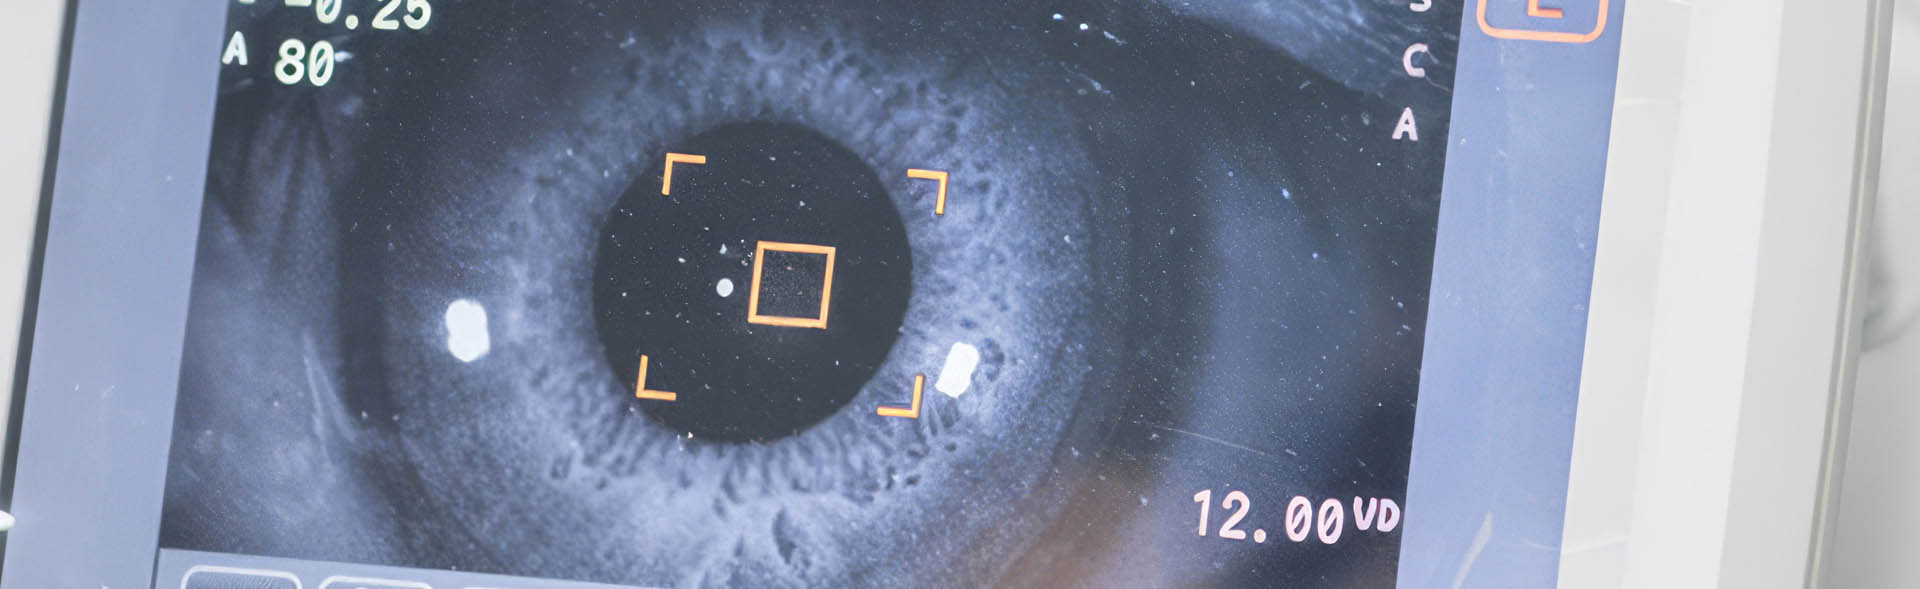

Pregled, dijagnoza i lečenje bolesti žute mrlje (makule) odnose se na savremene oftalmološke procedure koje omogućavaju rano otkrivanje i terapiju promena u centralnom delu mrežnjače. Ove metode se koriste kod oboljenja kao što su makularna degeneracija, kao i kod drugih degenerativnih i vaskularnih poremećaja koji utiču na centralni vid. Dijagnostika uključuje detaljne preglede poput OCT i drugih naprednih snimanja, dok lečenje može obuhvatati intravitrealne injekcije, laser ili hirurške procedure, u zavisnosti od stadijuma bolesti. Cilj je očuvanje i poboljšanje centralnog vida uz individualno prilagođen terapijski pristup.